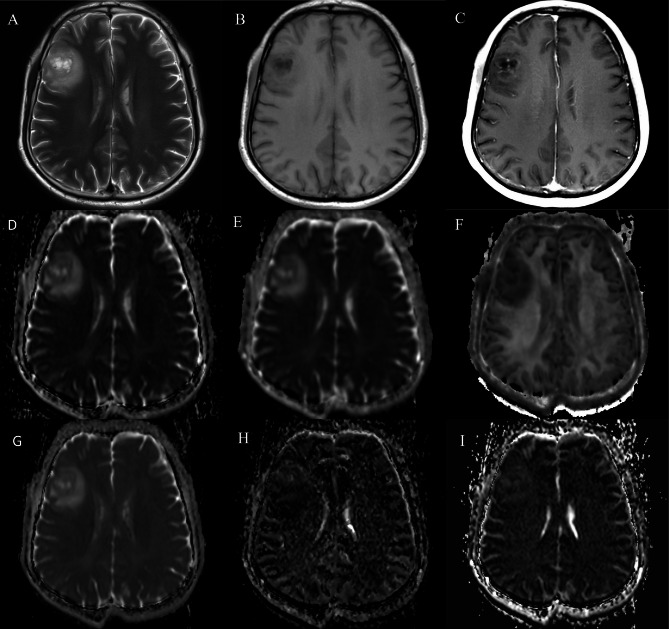

Methods and materials: A total of 422 participants who had DWI, DKI, and IVIM were enrolled between January 2020 and March 2024. The histogram characteristics of ADC, diffusional kurtosis(K), diffusion coefficient (Dk), pseudo-diffusion coefficient(D*), pure diffusion coefficient(D), perfusion fraction(f) in the solid component of tumors were calculated. Groups were compared by IDH genotype and 1p/19q codeletion status, utilizing logistic regression analysis and receiver operating characteristic curve to evaluate the differential diagnostic performance in predicting IDH and 1p/19q genotypes.

Results: Significant differences were observed in thirty-nine histogram-based features of diffusion parameters between IDH mutant gliomas and IDH wildtype glioblastoma. In IDH mutant gliomas, significant differences were found in thirty-six histogram-based features of DWI, DKI and IVIM parameters between those with and without 1p/19q codeletion. The IVIM model and the combined model showed superior diagnostic performance compared to the DWI model in terms of AUCs for predicting IDH mutations (0.903, 0.913 and 0.807, respectively p < 0.05), and 1p/19q codeletion in IDH mutant gliomas (0.825, 0.855, and 0.769, respectively; p < 0.05). Correlations between Ki-67 and the mean values of ADC, Dk, K, D, D*, and f were significant, with correlation coefficients from - 0.17 to 0.36 (all p < 0.05).